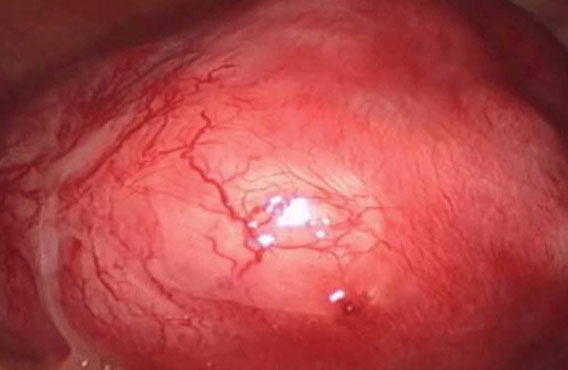

According to him, before now it was very difficult to diagnose it but that is changing now with the availability of better scanners, especially Magnetic Resonance Imaging (MRI) machines.

Ajayi added that adenomyosis which is common in women over 40 years comes with severe pains during menstrual period, noting that adenomyosis affects the quality of life of women due to the pains from the ailment.

He further said that a lot of cases of adenomyosis are being recorded from women who attend fertility clinic. According to him, while it is possible to do surgery to treat adenomyosis but because it is wide spread and might end up affecting the uterus reason it is usually advised that surgery is not a better option.

He also said that it is why women are told to see High-intensity Focused Ultrasound (HIFU) as an option to treating adenomyosis.